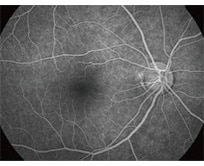

・蛍光眼底造影

蛍光色素の入った造影剤を腕の静脈から注射して、眼底カメラで眼底の血管を観察します。

血管の形や位置、血管からの血液中の水分のもれ具合などがわかります。

<正常>

<網膜中心静脈閉塞症>

<網膜静脈分枝閉塞症>

※検査の際には造影剤を注射するため、まれに吐き気や嘔吐、アレルギー反応などの副作用が起きることがあります。

検査中に何か異常を感じたら、速やかに医師に伝えてください。